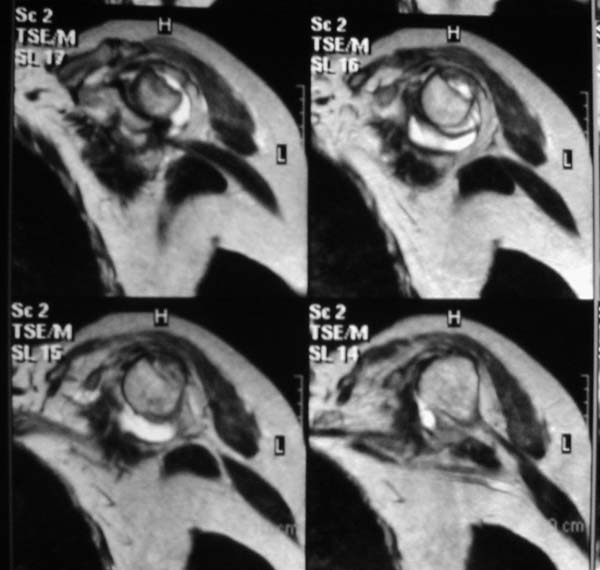

1

2

"Прицельная" съемка малопонятного очага.

Вопрос доктору Цориеву (для улучшения дальнейшей работы:) ).

В приложенном файле - МРТ изображение. Более информативно, чем предыдущий вариант? менее? или также?

А.Э. Цориев 25 Март 2003, 01:54

Все-таки, должен признать, что такие снимки - суррогат. Информативность чуть-чуть лучше, за счет большего размера. С учетом сложных топографо-анатомических соотношений необходимо иметь картину всех срезов, и смотреть их поочередно, иначе не создается целостной картины, а также иметь возможность манипулировать контрастом. Вот если б снимки были в DICOME - тогда от интерпретации было бы не отвертеться -)

А так, могу только сказать следующее

1. На рентгене - нижний подвывих плеча и очаг остеолиза суставного бугорка с четкими контурами (вдавленный перелом на фоне остеопороза ? доброкачественная опухоль? аваскулярный некроз ? (хотя ни разу не слышал об аваскулярном некрозе плеча..)

2.выраженный выпот в полости сустава

3. Сказать о связках и сухожилиях что-то при снимках в таком режиме не берусь.